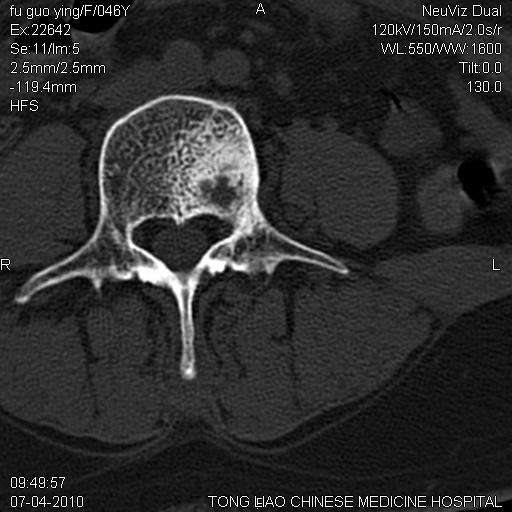

标题: CT27489:患者腰疼,其余椎体未见异常! [打印本页]

标题: CT27489:患者腰疼,其余椎体未见异常!

女性46岁,左髂骨溶骨性破坏+软组织肿块,考虑转移瘤,腰椎为退变/增生硬化/软骨下骨囊变。